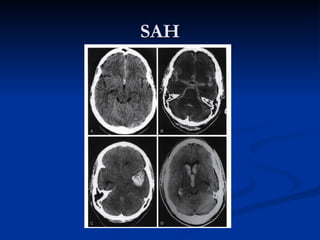

SAH

SAH diagnosis

   BCT

   Lumbar puncture : xantochromia

 Traumatic : serial CSF , clotting , xantochromia

 12 hours

 Contraindication : papilledema, coagulopathy

 Fresh CSF: low glucose

SAH classification

   Fisher ; brain ct